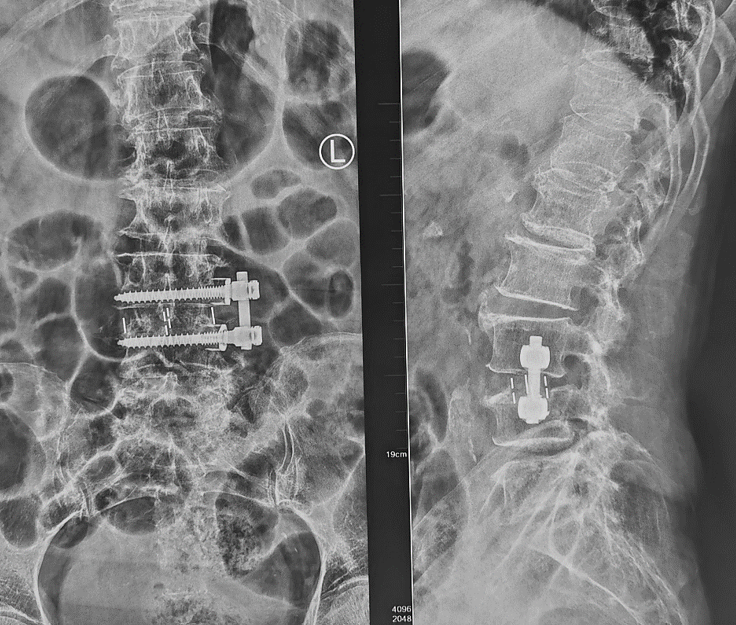

脊椎手術パーフェクト【電子版】 | 医書.jp。整形外科看護2025年1月号 | オンラインストア|看護・医学新刊。81W93nR9ipL._AC_UF1000,。令和6年三重県産コシヒカリ 10㎏。古晋徒手整骨中医馆| 腰椎间盘突出的6大“元凶”,你中招了吗。